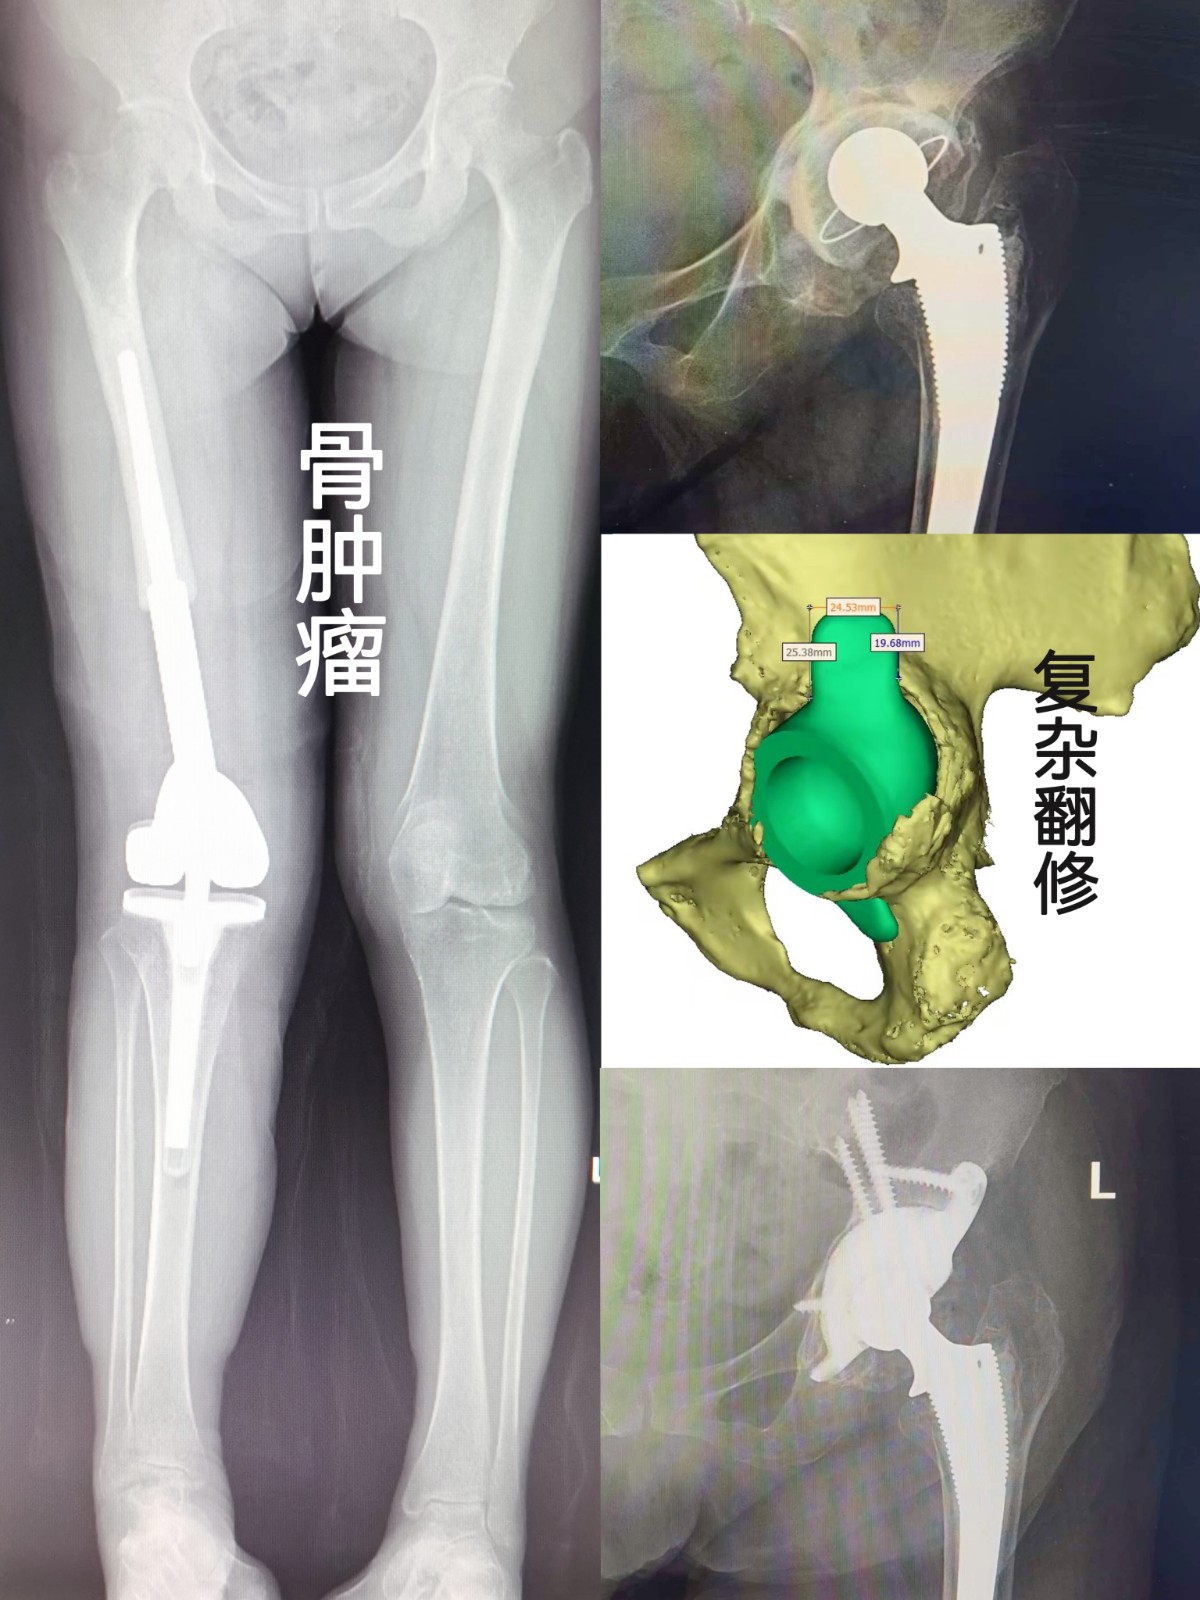

作為本地區(qū)創(chuàng)建最早的關節(jié)???,專業(yè)化特色明顯,關節(jié)手術復雜程度及手術量,均為本地區(qū)之最;可獨立開展各種肩、肘、腕、指、髖、膝、踝等關節(jié)的置換及翻修手術,特別擅長復雜髖、膝關節(jié)的置換、矯形、翻修,以及保膝階梯治療等。科室多年來在骨關節(jié)炎、關節(jié)畸形、股骨頭壞死,類風濕關節(jié)炎,強直性脊柱炎性關節(jié)病,髖關節(jié)發(fā)育不良,骨腫瘤,關節(jié)周圍骨折、脫位,以及關節(jié)運動損傷等疾患的治療中,積累了豐富的臨床經(jīng)驗。其中多種技術均為本地區(qū)首例獨家開展。

復雜髖翻修